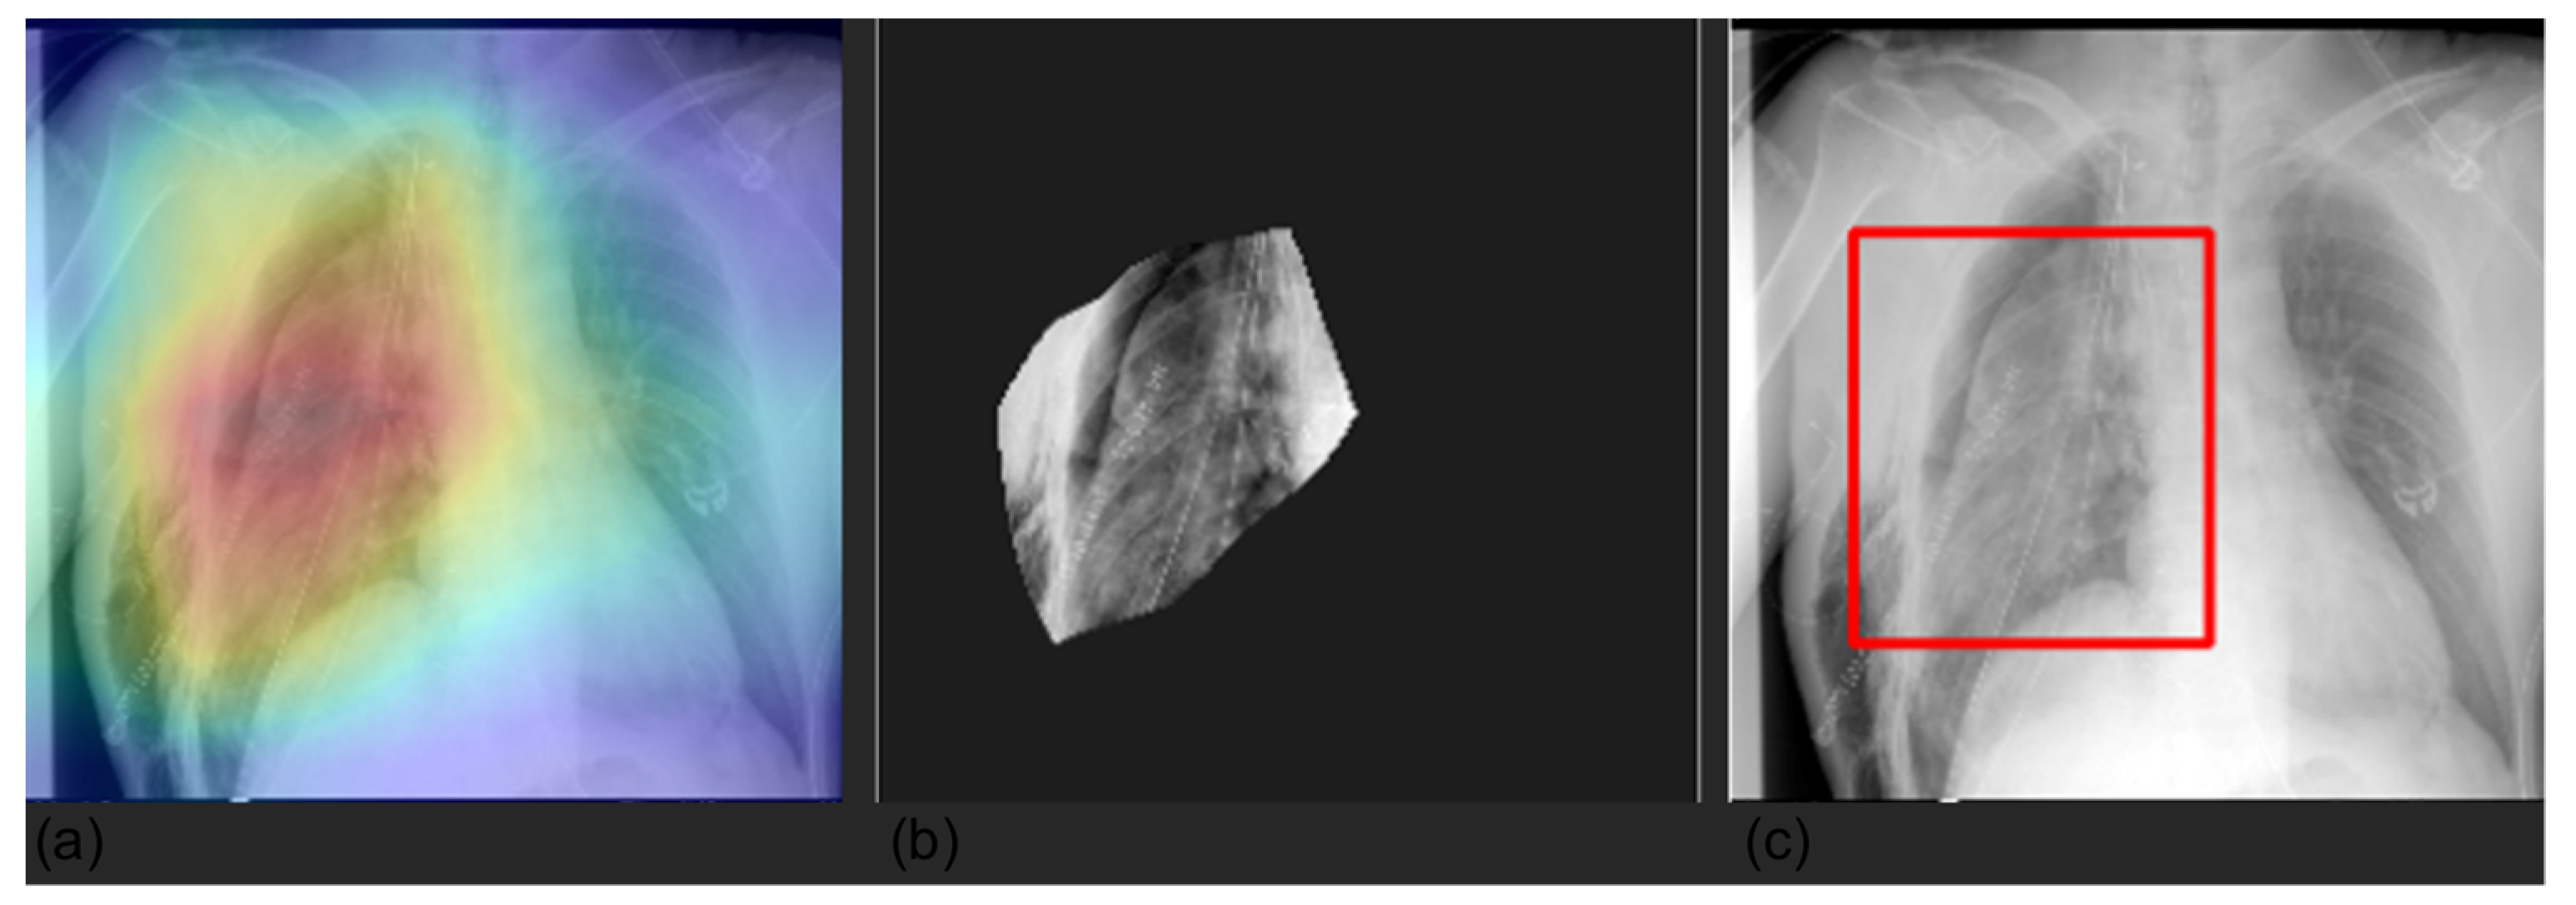

We averaged the saliency maps of two batches of 200 randomly sampled images computed with Grad-CAM. The Grad-CAM heat map emphasizes the salient area within the image in shades of red and yellow, whereas the rest of the image is colored in blues and greens. Figure 3 shows that at a population level, the model was generally focused on the lung field and did not take into account shortcuts or spurious correlations that could be present in the borders.

Figure 3.

Average of Grad-CAM saliency maps for two batches (panels a,b) of 200 randomly sampled images. Images confirm that the model focuses on the lung field (image in shades of red and yellow) and does not take into account shortcuts or spurious correlations that could be present in the borders.

We visualized the areas of the CXRs that the model predicted to be most indicative of each prediction using gradient-weighted class activation mappings (GradCAMs) [26] and by creating a bounding box surrounding it. Randomly selected examples are shown in Figure 4, Figure 5, Figure 6 and Figure 7.

Figure 4.

Visualization of pleura prediction maps for two selected CXRs. The panels represent the saliency mask obtained with Grad-CAM (panels a,d), the relevant area (mask values higher than the 0.8 quantile (panels b,e)), and the respective bounding box (panels c,f). The saliency mask focuses on plaura abnormalities, as shown by the heat map (panel a,d).